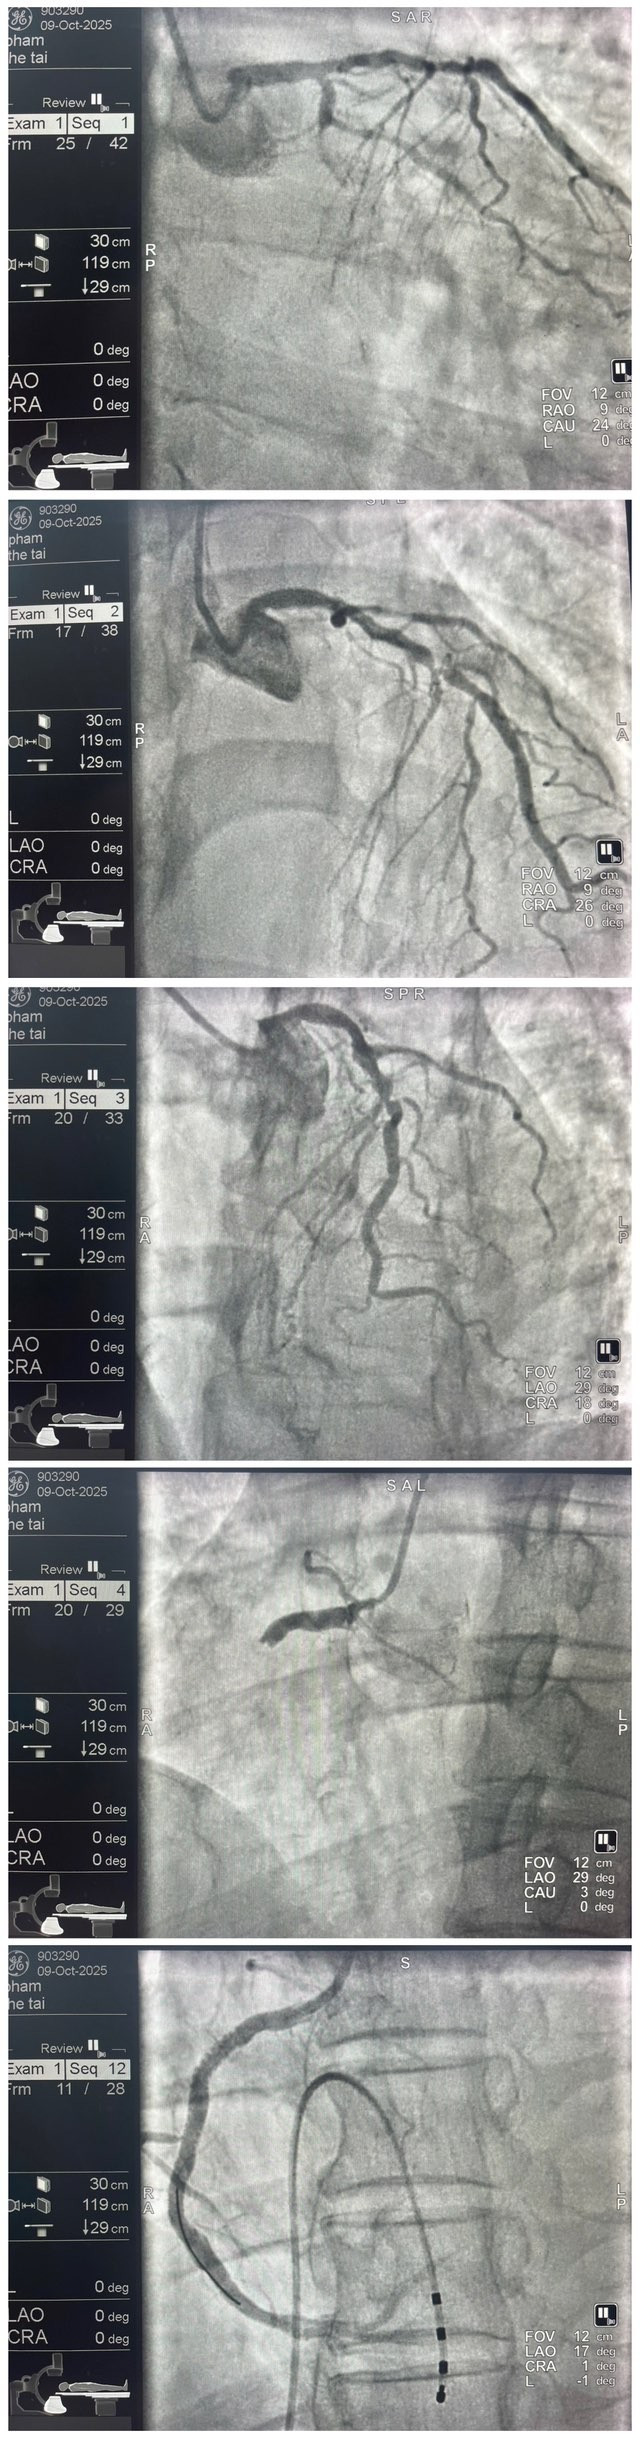

Tại phòng can thiệp, kết quả chụp mạch cho thấy bệnh nhân bị tắc hoàn toàn động mạch mũ (Cx), tắc hoàn toàn động mạch vành phải (RCA) và hẹp nặng động mạch liên thất trước (LAD).

Ngay sau khi chụp mạch vành, bệnh nhân xuất hiện rung thất và rối loạn nhịp tim liên tục. Ê-kíp can thiệp đã kịp thời sốc điện chuyển nhịp, đặt nội khí quản, thở máy và sử dụng ba loại thuốc vận mạch gồm adrenaline, noradrenaline và dobutamine để duy trì huyết động ổn định.

Sau khi kiểm soát được tình trạng nguy kịch, các bác sĩ tiếp tục tiến hành can thiệp động mạch vành phải, lấy huyết khối, nong bóng và đặt stent tái thông mạch, giúp dòng máu được lưu thông trở lại bình thường.